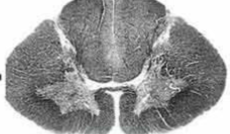

cervical

knowt flashcard image